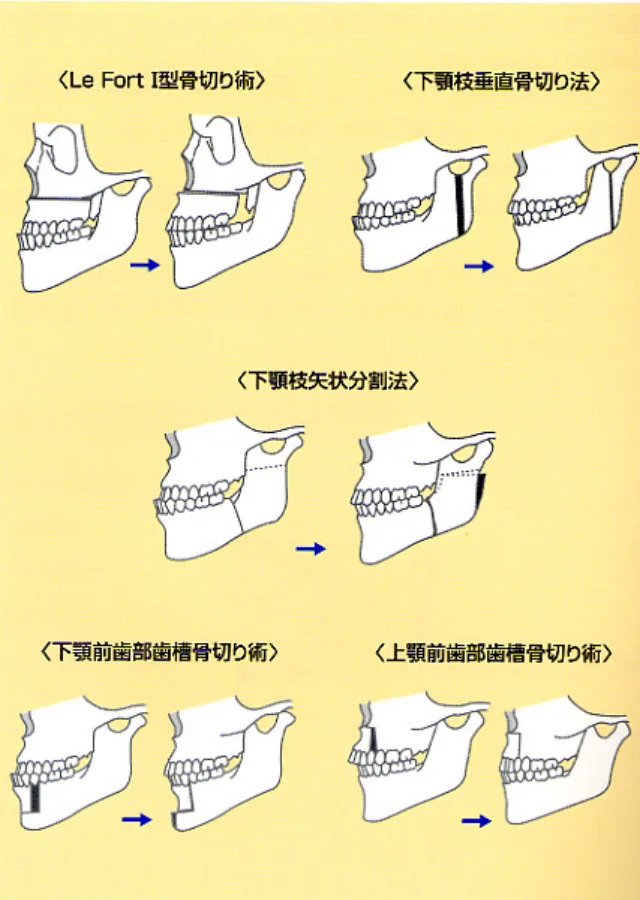

外科矯正手術(セットバック手術など)はどんな場合に適している?

セットバック手術(前方分節骨切り術)は、骨格が原因で起こる重度の出っ歯や受け口、口ゴボなどを根本的に改善するために行われる外科的な矯正方法です。歯列矯正だけでは十分に後退しきれない顎の突出を、直接骨を切り、適切な位置に移動させることで治療します。フェイスラインを整えられることから美容整形的な要素も含まれますが、その一方でリスクやダウンタイムがあるため、慎重に検討が必要です。

セットバック手術(前方分節骨切り術)の流れは?手術前後のスケジュールと注意点

セットバック手術を受ける場合、以下のような流れになります。

- 術前検査・カウンセリング(CT撮影・シミュレーション)

- 術前矯正(必要な場合)

- 手術(入院1~2週間)

- 術後リカバリー(1~3ヶ月)

- 仕上げの矯正(必要に応じて)

手術後は腫れや痛みが伴うため、十分なダウンタイムを確保することが必要です。最近では、治療期間短縮のために先にセットバック手術を行い術後矯正を行う流れもあります。